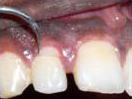

An Innovative Technique of saving a Tooth with Fracture Extending Sub-Gingivally (Chisel Type Fracture)

Tooth with Fracture Extending Sub-Gingivally

Showing picture line

Extending Palatally and

Sub-Gingivally.